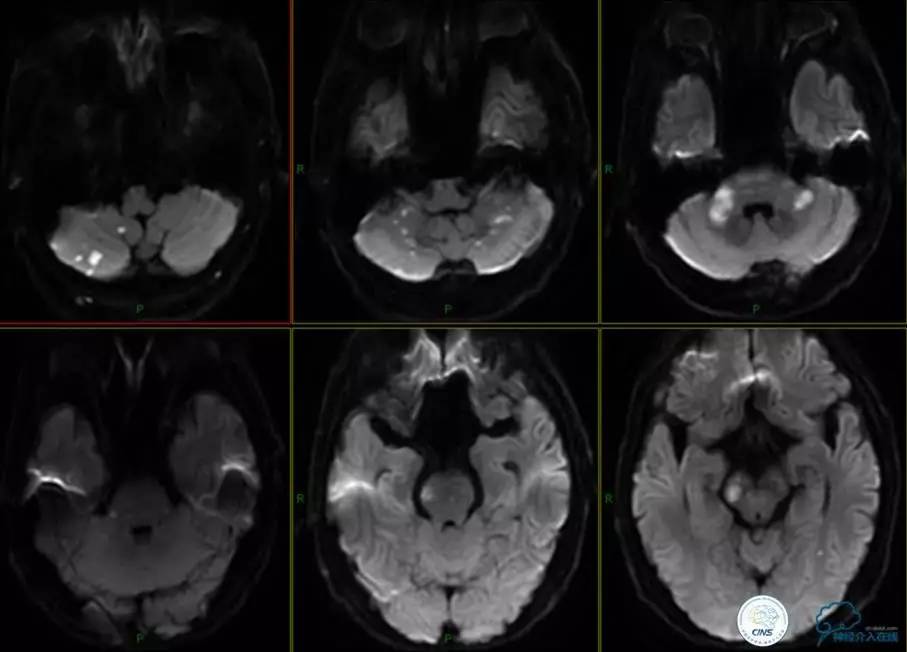

▼头颅MR

患者:男性,59岁,主诉“头晕伴行走不稳3日,言语含糊1日”。

既往史:高血压病史,冠心病病史,吸烟史多年。

查体:构音障碍,吞咽功能障碍,左侧鼻唇沟浅,伸舌左偏,左侧指鼻试验阳性,闭目难立征阳性,左侧肢体肌力Ⅲ级,肌张力增高。

实验室检查:

甘油三酯为3.68mmol/L↑,总胆固醇为6.62mmol/L↑,空腹血糖为6.86mmol/L↑,低密度脂蛋白为4.56mmol/L↑。